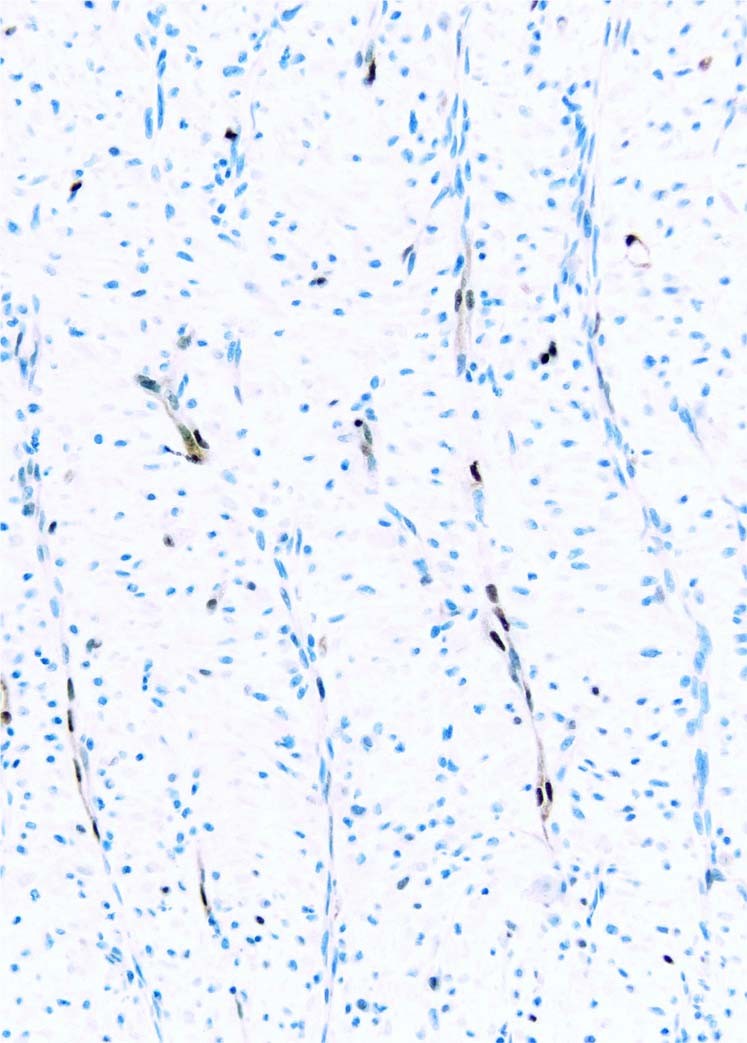

Fig. 1

From: Cyclin D1 immunohistochemical staining to separate benign from malignant mesothelial proliferations

Prominent cyclin D1 staining in vascular endothelium in a case of organizing pleuritis. Although staining is strong when present (and serves as a good internal control when positive), it is very patchy. In this case the spindled mesothelial cells are negative